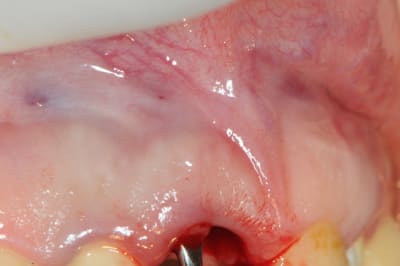

le périoste est décollé de la table externe sur tout le pourtour de la déhiscence en passant par l'avéole de l'extraction. pas de lambeau.

une membrane est insérée entre le périoste et l'os et repose sur les bords de la déhiscence. c'est la partie la plus dificile à faire.

peu visible sur la photo, mais une fois la membrane en place, elle affleure avec le bord cervicale.

je suis de plus en plus convaincu que l'interposition de la membrane en recouvrement sur la déhiscence et entre le périoste et l'os est la meilleur solution.

le fait de mettre une couronne provisoire permet de fermer complètement le site d'intervention ce qui assure en fait la meilleur cicatrisation.

8-11 décolement du périoste de la table externe en passant par l'alvéole

12-15 insertion délicate de la membrane